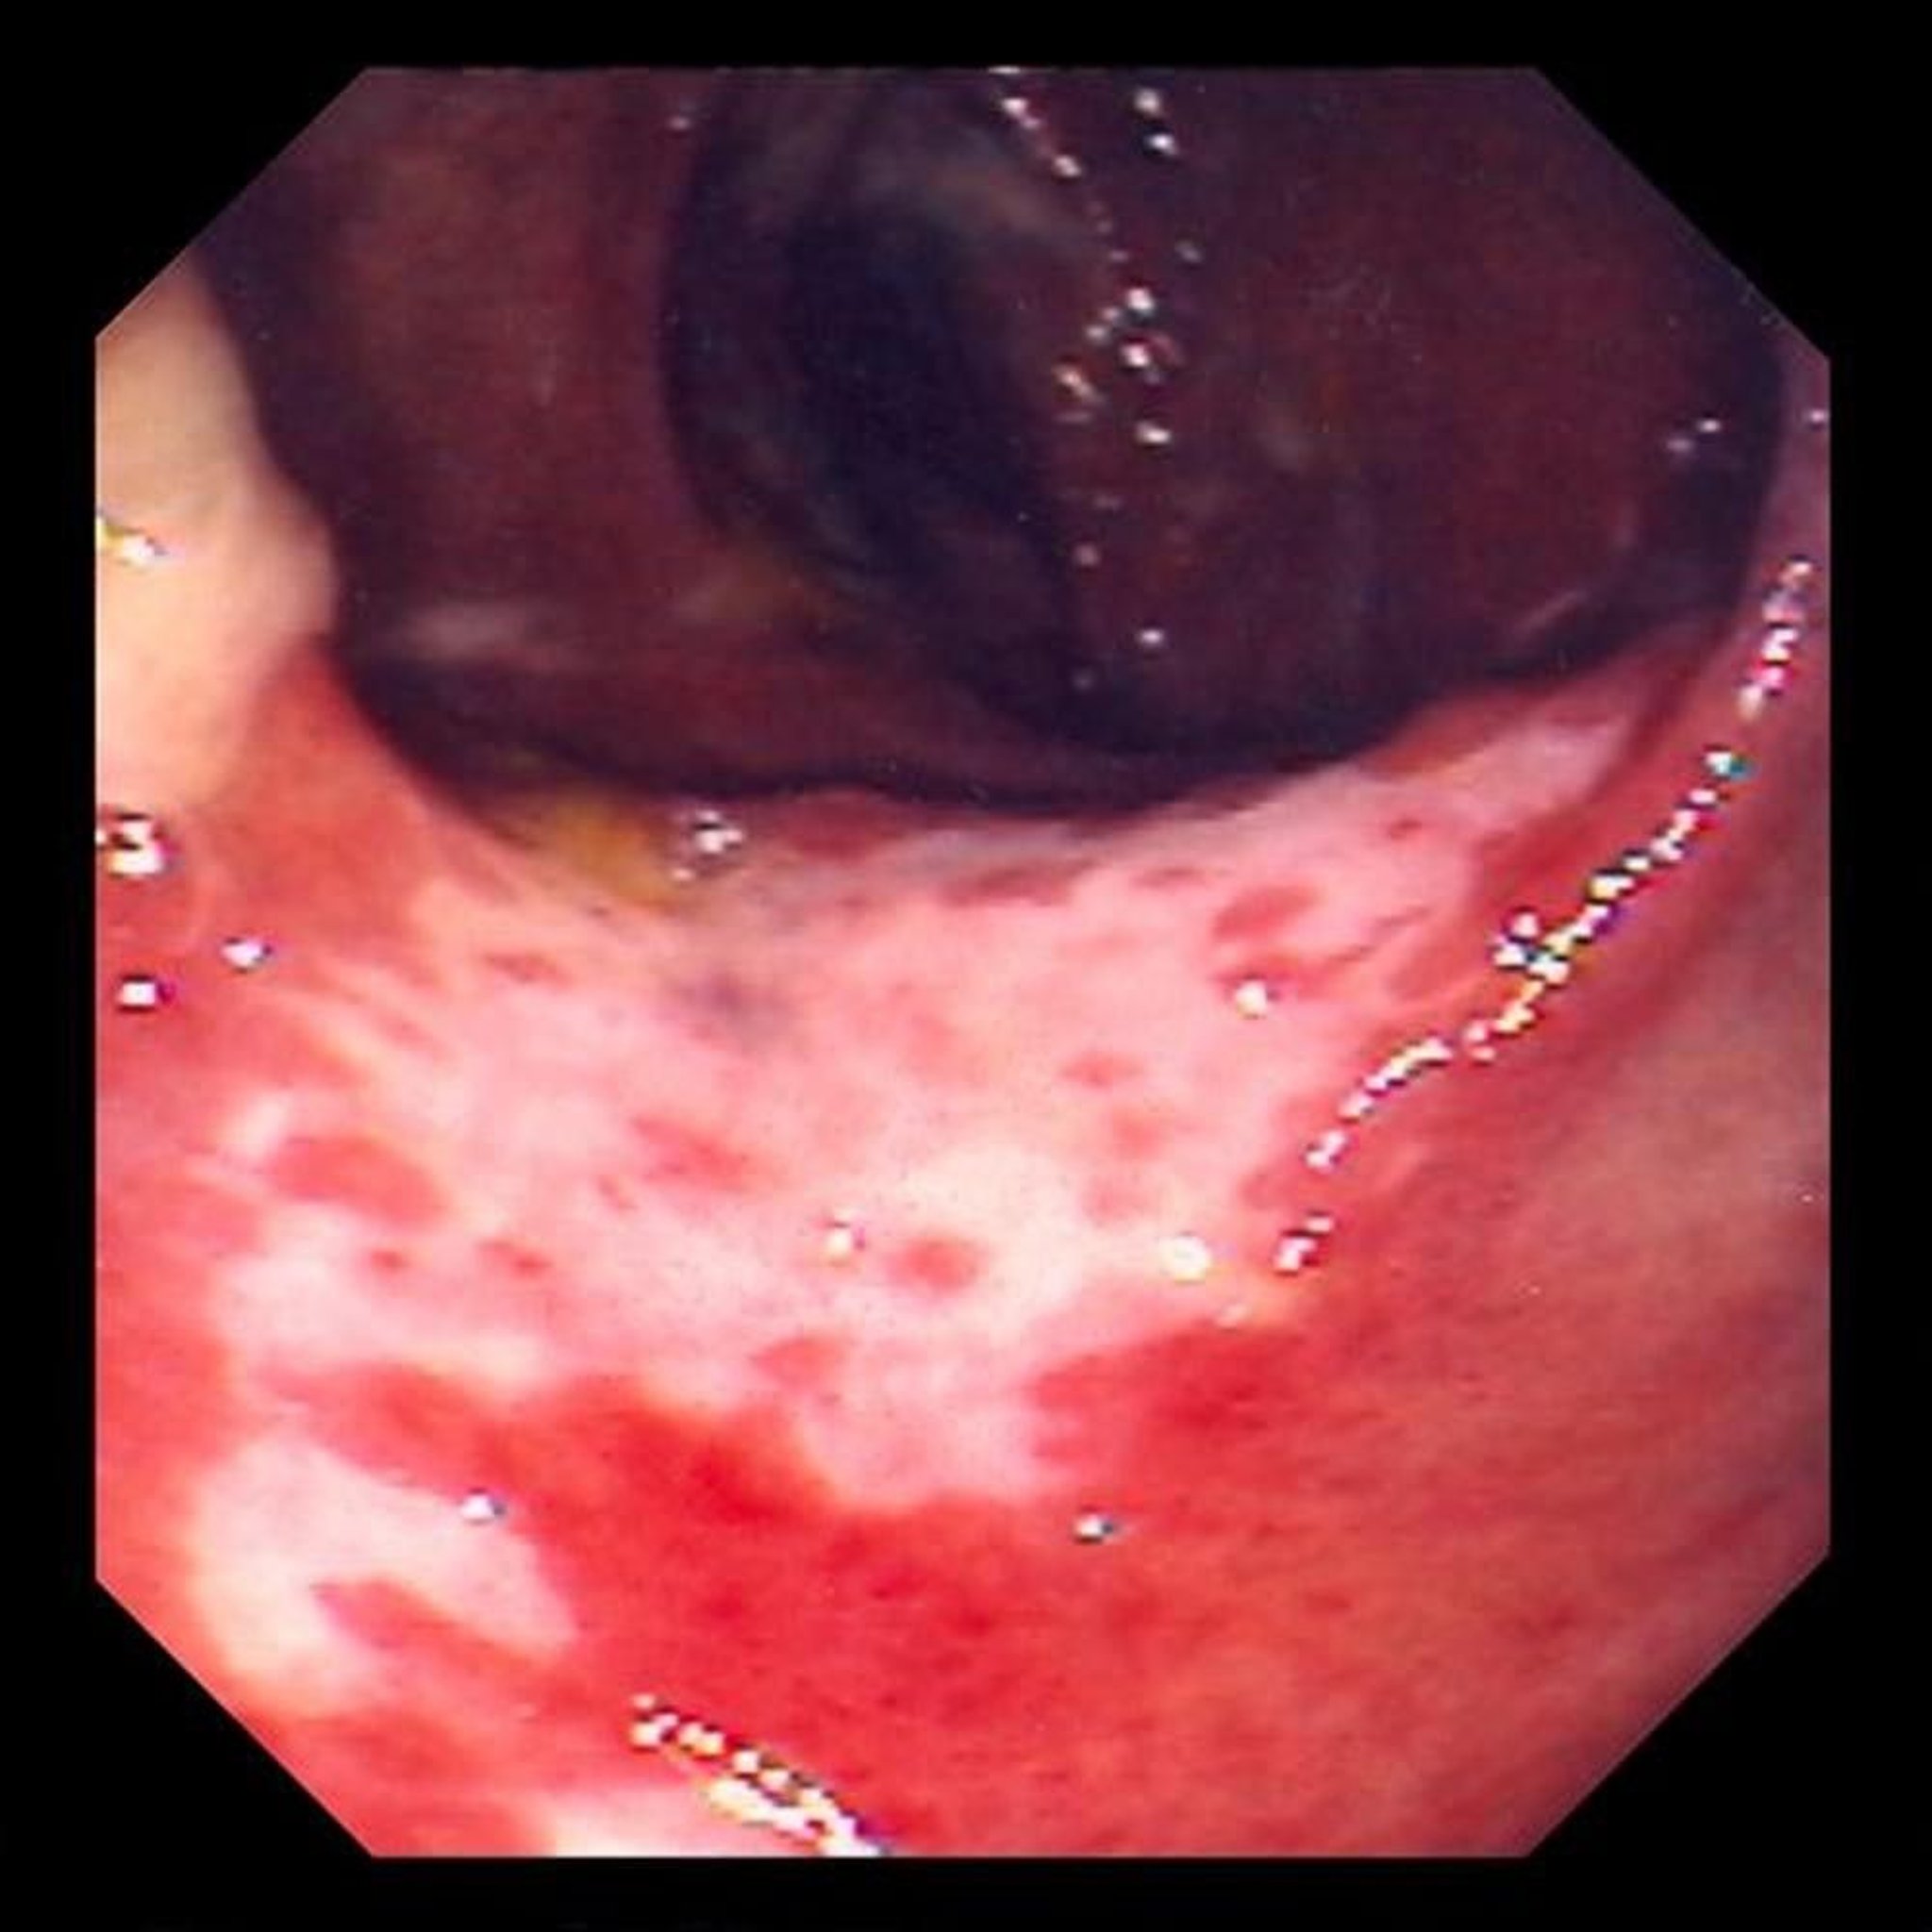

Kolaitisi ya Ischemic (Kolonoskopia)

This photo shows damage to the lining of the intestine caused by blockage of blood flow. The lining of the intestine is red and covered with ulcers (the white areas).

Photo provided by David M. Martin, MD.